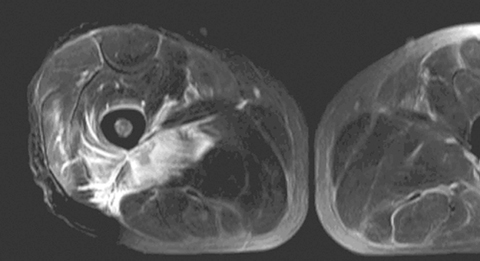

MRI helped in making the diagnosis and delineating the extent of the muscle involvement in all patients, as (see Box 2) the high signal intensity of the pathological process (prolonged T2) can be easily distinguished from the relatively low signal intensity of normal muscle (shortened T2). The superiority of MRI for differentiating pyomyositis from other pathological processes, outlining the extent of involvement and localising fluid collections, has been previously reported.8 The ability of MRI to obtain multiplanar contiguous sections provides excellent anatomical detail of each muscle group and precisely locates the site of disease. MRI scans in 43 cases of pyomyositis found that hyperintense signals on T2-weighted images were detected in all patients.18 A hyperintense rim on unenhanced T1-weighted images and peripheral enhancement after gadolinium injection was useful for identifying the number, size and location of soft tissue abscesses.18